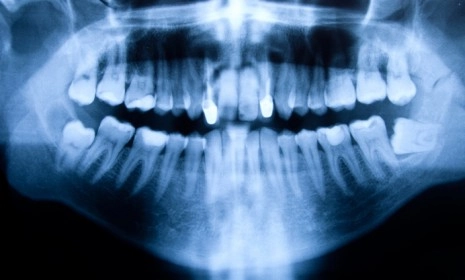

Patients with tumors were more than twice as likely to have had a specific kind of X-ray — called a "bitewing" — one or more times a year. Bitewings, in which a patient bites down on X-ray film, take photos of the upper and lower back teeth. Another X-ray called a "panorex" — which takes a panoramic shot of the teeth, sinuses, and jaw — was also associated with an increased risk of meningioma, particularly if the patient started getting them regularly before age 10.